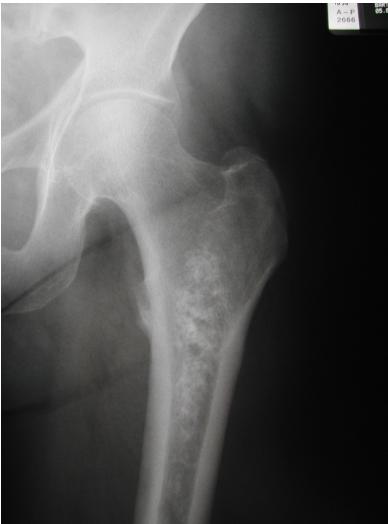

Popcorn, cartilaginous - chondrosarcoma usually - even though theres no perosteal reaction

site: distal femur size: Most (involving how much? / cm?) matrix: mixed - mainly radiopaque , wide zone of transition, cortical destruction, resulted periosteal reaction, and codman’s triangle soft tissue involvement: